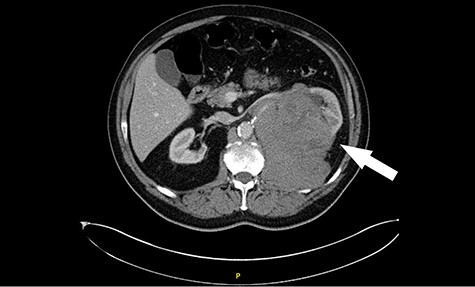

His CT scan identified large left renal tumour invading psoas muscle. Left mid ureteric tumour as well. Multiple regional nodes. No hepatic, pulmonary or osseous metastasis. The scan was highly suggestive of metastatic transitional cell carcinoma (Figs. 1 and 2).

Computed tomography (CT) revealing a large insinuating left renal soft tissue mass measuring 140 × 105 mm.